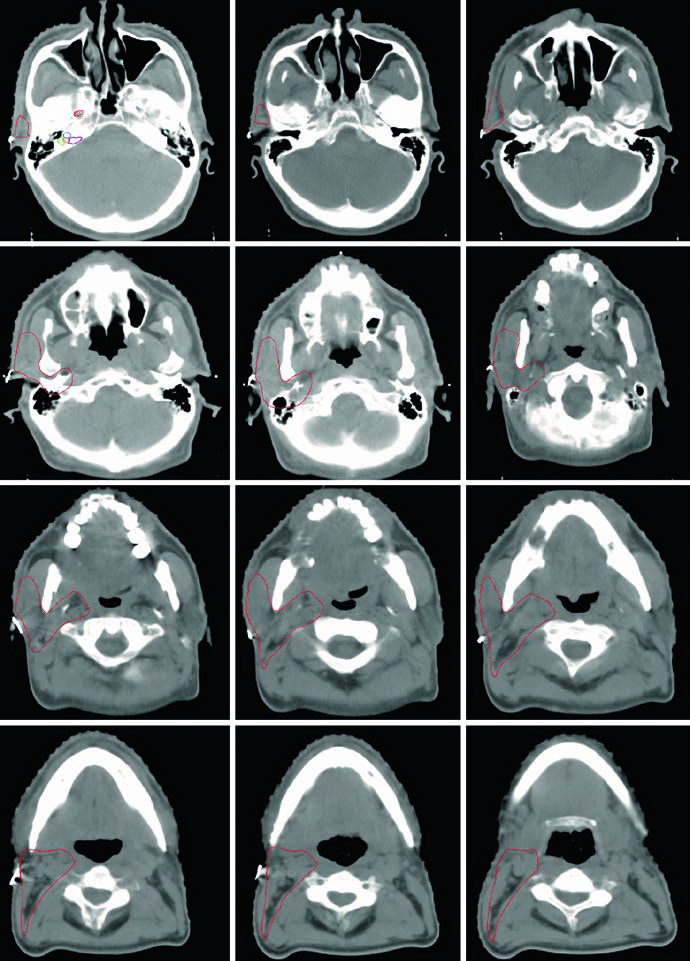

The CT images demonstrate the glossopharyngeal nerve pathway through different axial slices. The nerve can be identified posterolateral to the styloid process, descending alongside the internal carotid artery. The red oval marking across slices indicates the expected nerve location along its cervical course. The final slice uses soft tissue windowing for improved visualization of the relationship between the nerve and cervical vessels.

Mastering this anatomy is especially relevant when planning radiation for parotid adenoid cystic carcinomas, given their strong tendency to follow nerve sheaths. Including the full course — from the jugular foramen to the pharyngeal branches — ensures that subclinical spread along the glossopharyngeal nerve is adequately covered. A similar neural mapping approach is discussed in the context of unknown primary tumors of the head and neck.